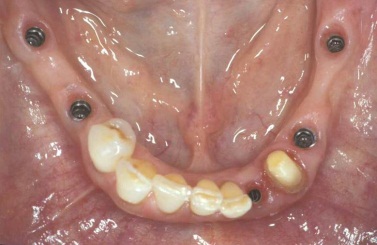

Bezzubá čelist je hlavní indikací pro ošetření pomocí implantátů. Zejména celkové zubní náhrady v dolní čelisti mají velice nízkou stabilitu a držení díky velkému úbytku kosti.

S pomocí zubních implantátů můžeme díky různým kotevním systémům (třmeny, kulové hlavy, Locatory) zajistit stabilitu a držení protézy nebo při použití většího počtu implantátů zhotovit pevné náhrady – můstky nalepené nebo našroubované na pevno na implantáty.

S těmito typy náhrad můžeme dosáhnout perfektní funkci, výbornou estetiku, fonetiku a současně zajistit u pacienta možnost dobré hygienickou péče a čištění, která je pro životnost implantátů velice důležitá.